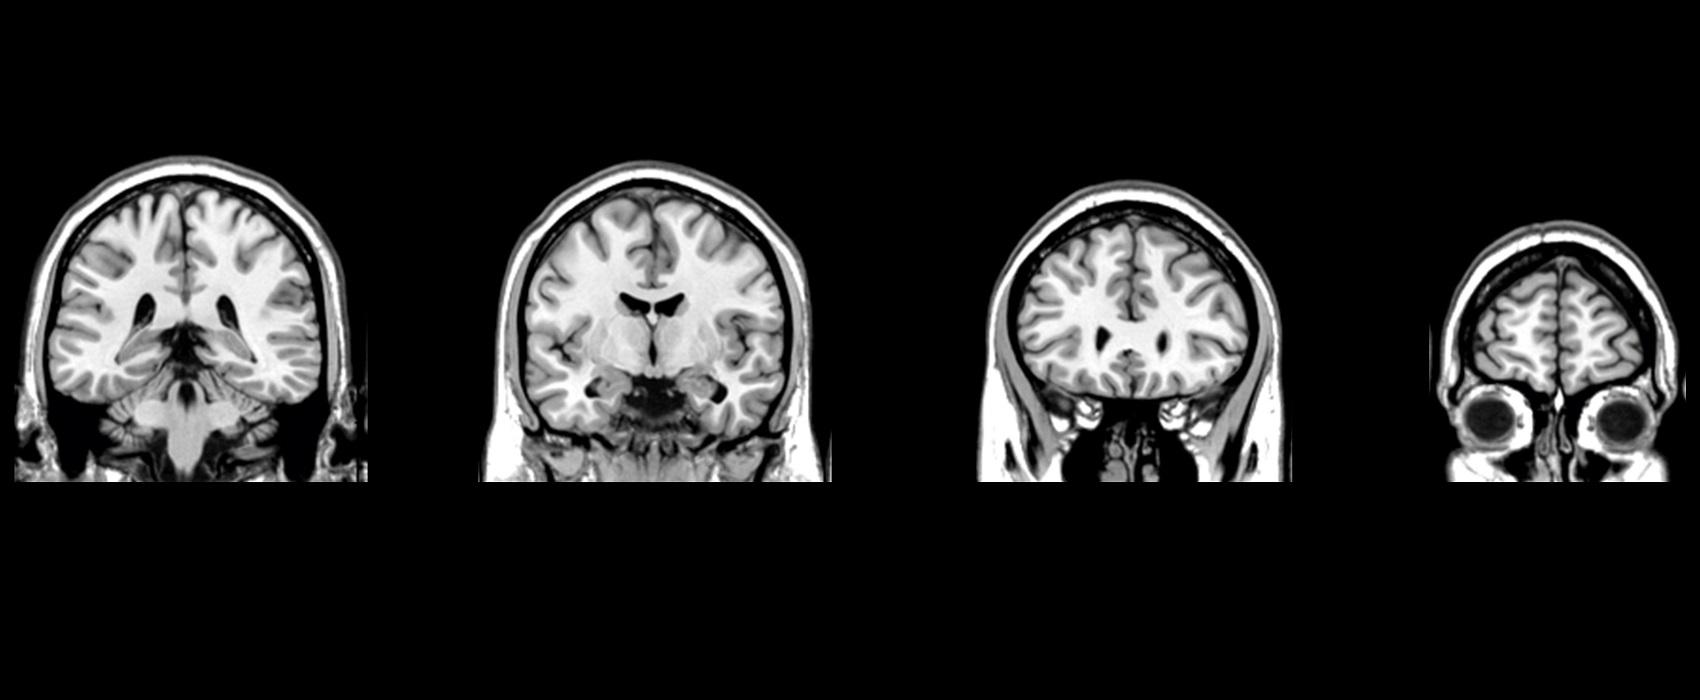

A esquizofrenia pode estar relacionada a alterações de neurodesenvolvimento, incluindo a incapacidade do cérebro de criar um sistema de vascularização...